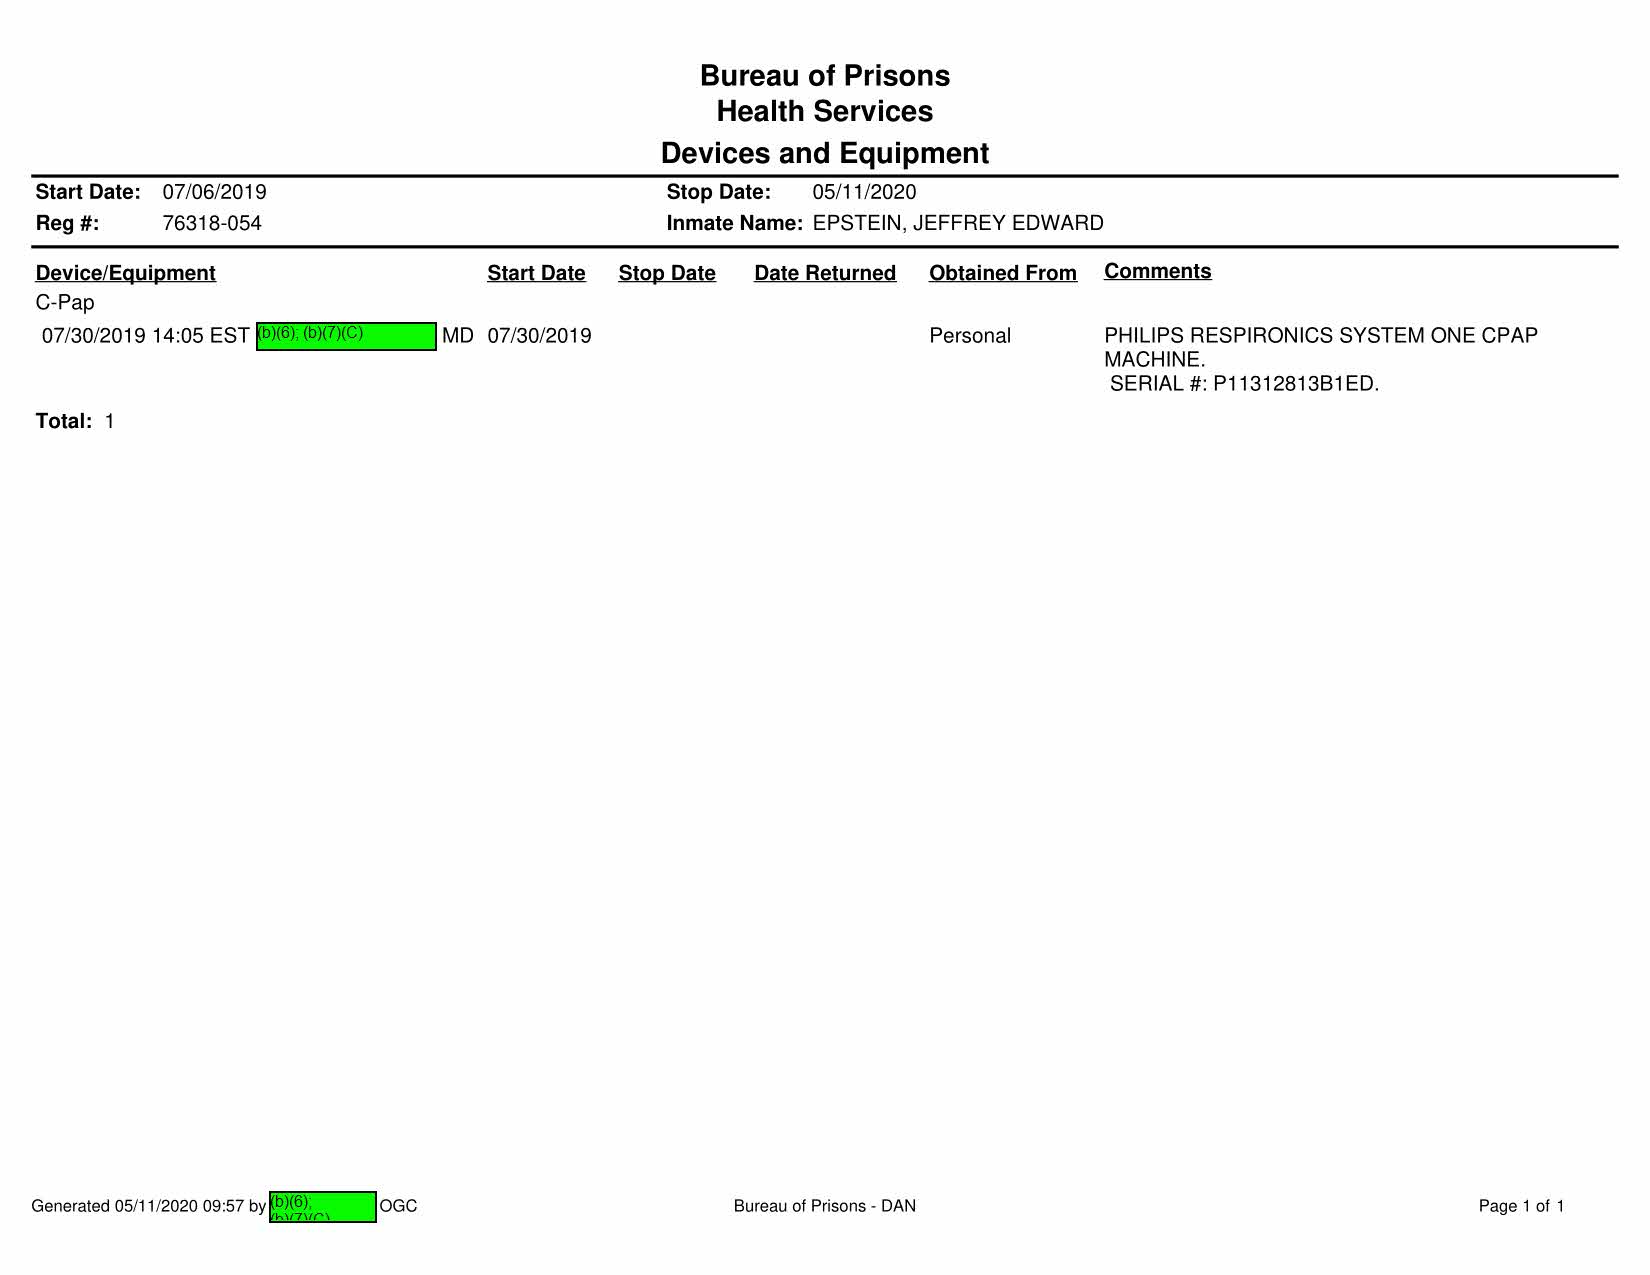

Fwd: Jeffrey Epstein, 76318-054 From b)(6); (b)(7)(C) To Executive Stafff._b_X5_>;_<b_X7_><_c> ______ __. Date Subject: Attachments: Good morning all, b)(6); (b)(7)(C) 2019/07/26 10:10 Fwd: Jeffrey Epstein, 7 6318-054 TEXT.htm Epstein's attorneys are trying to get him his CPAP machine per our request. Can we have them hand-deliver it to medical staff as we have in previous instances? Thank ou, b)(6); (b)(7)(C) > > ~ b)(6); (b)(7)(C) Mr. }~i~,., I l@gmail.com> 7/26/2019 9:50 AM > > > Is Mr. Epstein approved to receive a CPAP machine? If so, should we send it directly to him through the inmate mail system? Please confirm. Thank you. b)(6); (b)(7)(C) Page 747